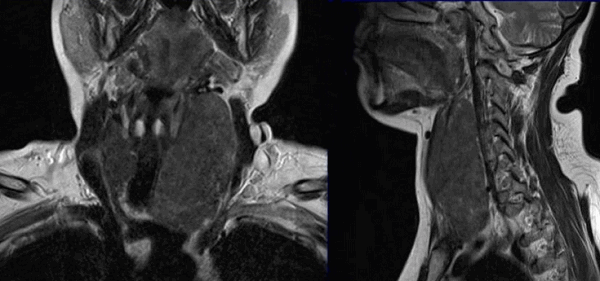

Онкологический процесс на томограммах щитовидной железы

Метастазы на снимках МРТ шеи

Врач-рентгенолог указывает в описании признаки злокачественного образования щитовидной железы, но окончательный диагноз ставят на основании дополнительных исследований (биопсии, клинических анализов и пр.)